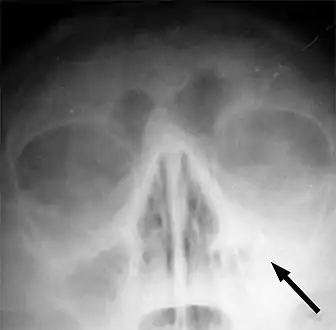

Imaging by either X-ray, CT or MRI is generally not recommended unless complications develop.[54] Pain caused by sinusitis is sometimes confused for pain caused by pulpitis (toothache) of the maxillary teeth, and vice versa. Classically, the increased pain when tilting the head forwards separates sinusitis from pulpitis.

For cases of maxillary sinusitis, limited field CBCT imaging, as compared to periapical radiographs, improves the ability to detect the teeth as the sources for sinusitis. A coronal CT picture may also be useful.[37]